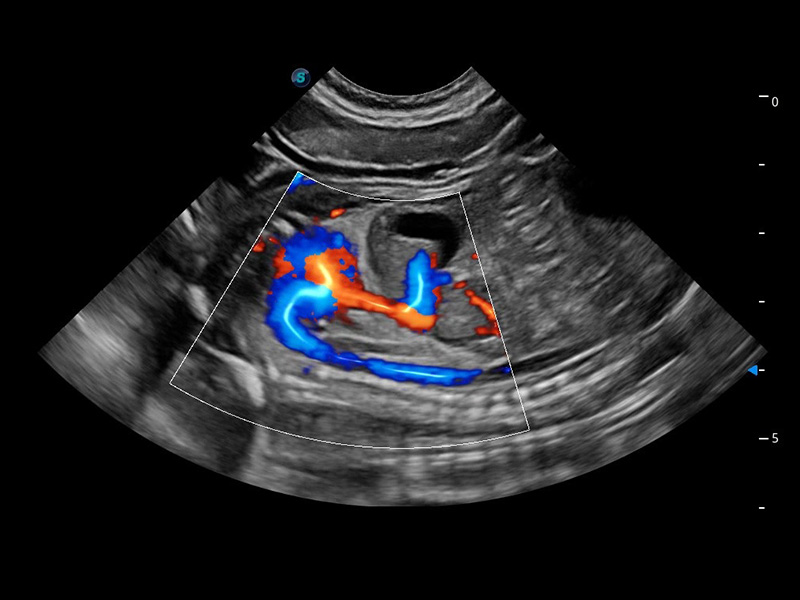

ProPet 60 作为一款高端台式动物超声设备,为动物医生的日常诊断提供了一系列贴合动物临床需求、解决临床实际问题的高级成像功能。凭借全系列高清探头,满足医生对腹部、心脏、生殖、浅表、肌骨等成像的所有需求,切实帮助您提升检查效率,提高诊断信心。

动物是人类最亲密的朋友和最值得信赖的伙伴。银河优越会也一直致力于探索动物专用的超声影像解决方案。 全新推出的ProPet系列,是银河优越会在动物超声影像智能化、专业化、精准化的一次跨越式革新。动物不能用言语来表述自己的不适,通过超声影像,ProPet系列搭建了动物医生与不同物种沟通的“桥梁”,为动物医生注入了“治愈之力”。